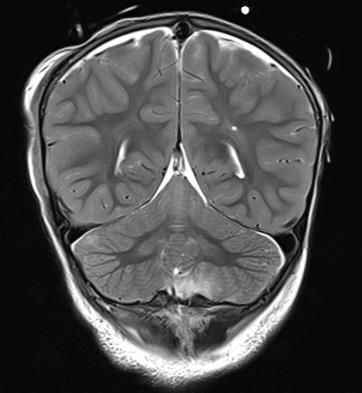

Brain and Spinal Cord MRI:

- Cranio-spinal trauma;

- Probable dissection of the right internal carotid artery;

- Aneurysm with subarachnoid and ventricular hemorrhage.

CT Scan of the Brain, Facial Mass, and Spine:

- Multiple fractures of the skull base and cranial vault;

- No vertebral fractures (no spinal cord compression);

- Displaced fracture of the mandibular condyle and right orbital floor;